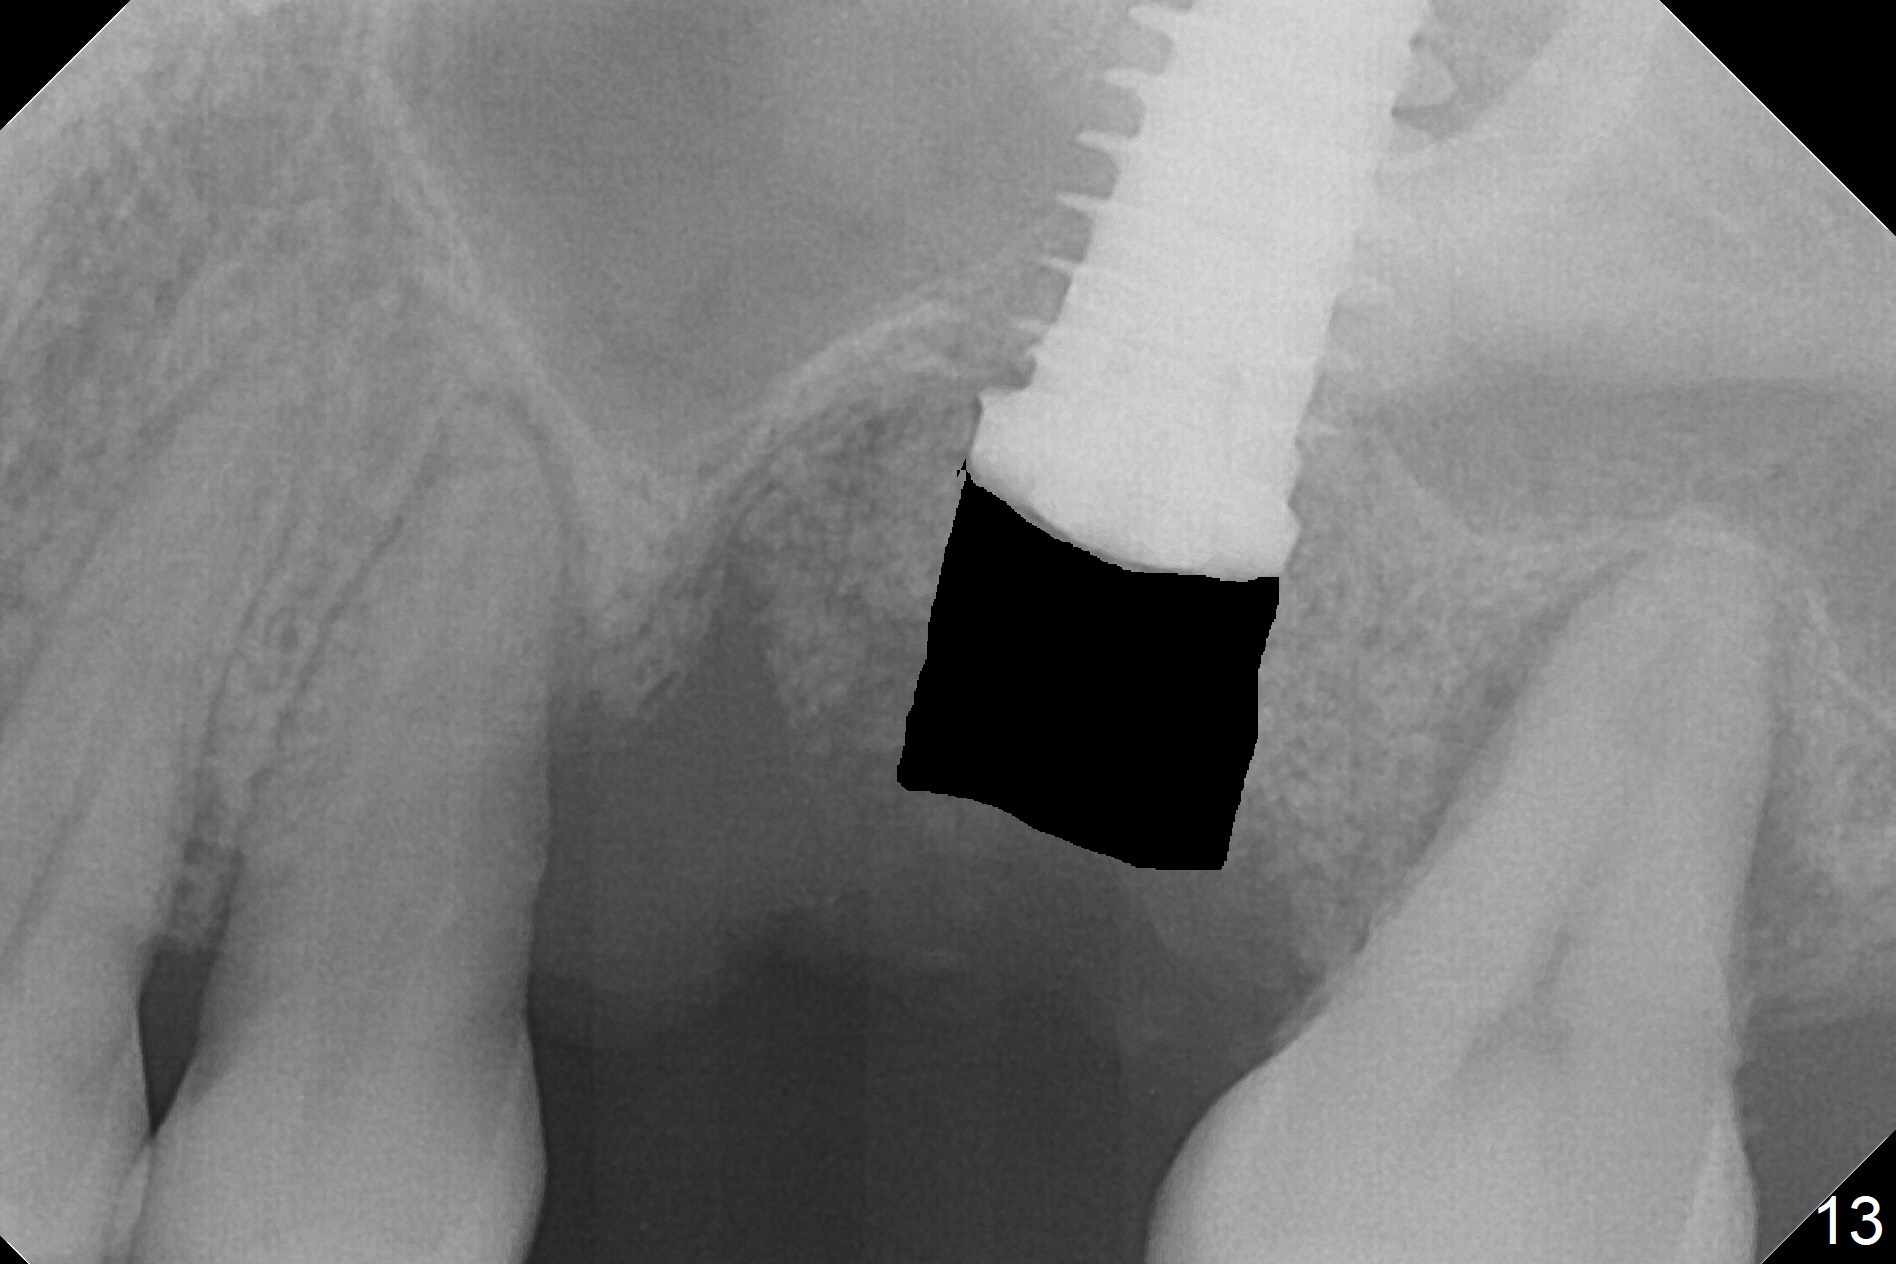

Questions for Dr. Wang: Can we remove the coronal portion of the bone (Fig.13) and back up the implant (Fig.14 arrow) 4-5 months postop for easy restoration?  If it is not a good option, can we produce pair abutments with 5 and 7 mm cuffs?